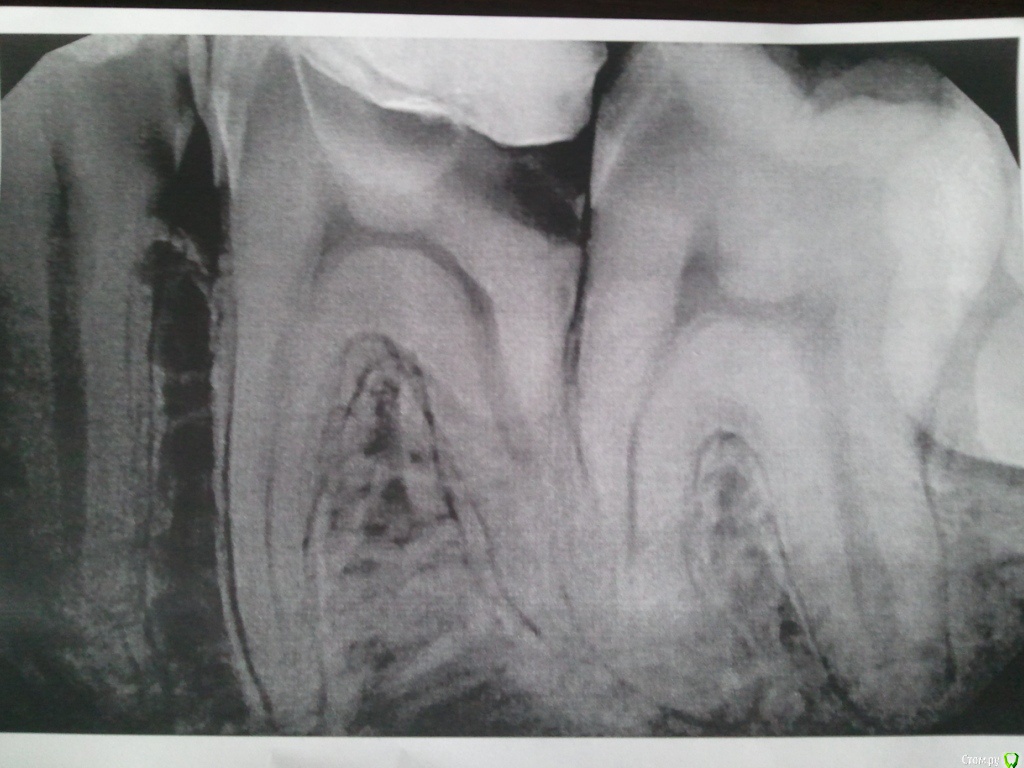

LexIgnatov Опубликовано 1 декабря, 2015 Автор Поделиться Опубликовано 1 декабря, 2015 (изменено) Здравствуйте. Вновь прошу совета.Итак, в "предыдущих сериях"... Шестой зуб слева для меня (Или справа глазами доктора).Исходное состояние перед лечением:Не очень понимаю что где, но для лечения обратился потому что отвалилась пломба на этом зубе.17.11.2015 Убран глубокий кариес, положена какая-то мазь для заживления-успокоения нерва. Через день нерв начал стрелять.20.11.2015 Положили параформальдегидную (насколько я понял) пасту для умерщвления нерва (позже выяснилось что там 4 канала). Боли сменились на лёгкие ноющие с редкими покалываниями.23.11.2015 Сделан снимок ОПТГ.Записали на приём 5.12.2015 к стоматологу-ортодонту, чтобы решить что делать с 7 и 8 зубами. Дело в том, что 7-й зуб наполовину сверху прикрыт десной. А на открытой части виден кариес. Сказали что если ортодонт скажет, что можно сохранить 7 и 8 зубы, то нужно удалить часть десны над 7-ым и попробовать вылечить кариес. Говорят что судя по снимку нервы в нём можно будет не удалять. Пугает, что когда 6-й лечили, тоже говорили, что попытаются сохранить нервы - однако после болей пришлось их удалить. Проблема в том, что у меня рот плохо открывается, и если потребуется депульпирование 7-го, то туда будет очень сложно залезть. Другой вариант как они сказали - удалить 7-ки, а через их полость удалить и 8-ки. Но это меня пугает, всю челюсть перепахают. У матери (50 лет) 8-ки до сих пор не прорезались и не беспокоят.27.11.2015 Удалили 4 нерва в 6-м зубе без анастезии. Два нерва удалялись с болью несмотря на девитализацию, сделали внутрь каналов местную анестезию - пошло лучше. Во время чистки каналов где-то сильно дёргало, чистили пока не перестало дёргать. Поставили гуттаперчи с противовоспалительным раствором и временную пломбу на 11 дней. Сказали что потом будут ещё раз чистить каналы и пломбировать их на постоянку. Зачем второй раз чистить? Не хочу снова подпрыгивать в кресле))Снимок в процессе установки гуттаперчи:PS. Ещё не понятно как восстановить коронковую часть зуба. От него фактически остались две стенки - со стороны щеки и языка, а остальное пломба. Хочется понять как грамотнее поступить, что посоветуете? Спасибо.PS2. Редкие слегка покалывающие боли сейчас (пока лежит противовоспалительное) в моём случае нормально или нет? Иногда ощущение, что от пульса отдаёт, при приседании. А иногда даже от активной мимики. Или это может реагировать плохой соседний пятый зуб? И можно ли есть на таком зубе? Я вот побаиваюсь и ем на другой стороне. Изменено 1 декабря, 2015 пользователем LexIgnatov Ссылка на комментарий